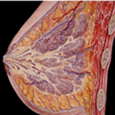

女性生殖系统包括内、外生殖器官及其相关组织。